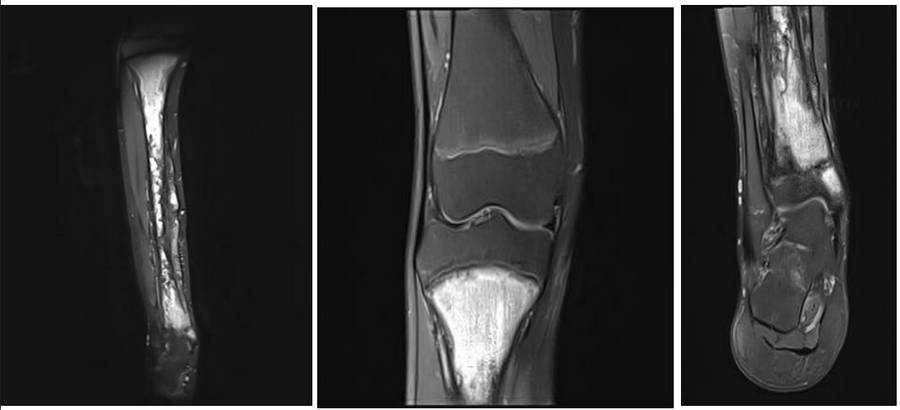

Ameliyat Öncesi: Röntgende tibianın tamamına yakınını tutan düzensizlik, harabiyet ve güneş patlaması görünümde periost reaksiyonu

Ameliyat Öncesi: MR’da tibianın üst epifizi hariç tamamını tutan tümör dokusu görülmekte